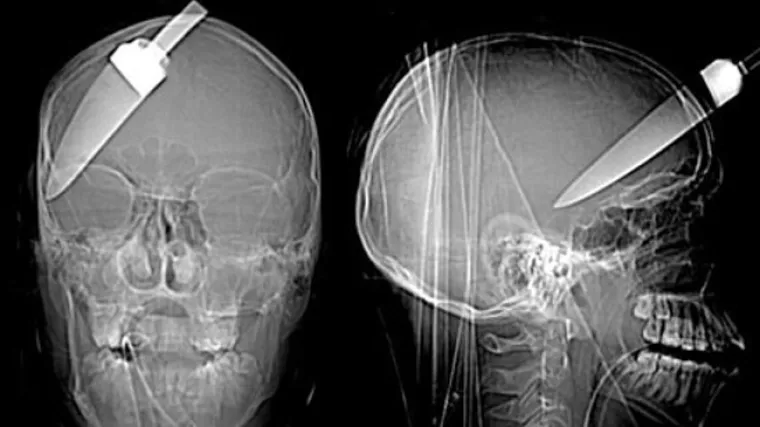

BOLJET ĆE VAS OD SAMOG POGLEDA... Rengenske snimke od kojih će vas proći trnci

Ovo mu je nagrada što je zaustavio pljačku.